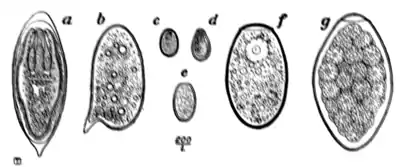

Fig. 168.—Ova of nematodes.

a, Strongylus subtillis; b, Ankylostomum duodenale; c, Trichiuris trichiura; d, Strongyloides starcoralis; e, Necator americanus; f, Ascaris lumbricoides; g, Ascaris lumbricoides (unfertilized).

rarely found in the stools, as these parasites do not, as a rule, part with their ova until the joints of the former, or the entire body of the latter, have left the alimentary canal; but as the three nematodes first mentioned pass their eggs directly into the bowel, these eggs habitually appear in the fæces and constitute unequivocal evidence of the presence of their respective parental forms. Occasionally the ova of hepatic and intestinal parasites, such as Schistosomum japonicum, S. mansoni, Clonorchis sinensis, Fasciola hepatica, Fasciolopsis buski, and other rarer helminths, are encountered. Without large experience the ova of the rarer parasites cannot be identified off hand; but if the practitioner has learned to recognize those of the three common species, he will at one know when he comes across the ova of any of the rarer species, and, on referring to some special work on helminthology, will have little difficulty in arriving at a correct diagnosis.

The points to be attended to in the diagnosis of ova are size, shape, colour, thickness, roughness, smoothness, and markings on the surface of the shell; the presence or otherwise

of yolk spheres, of a differentiated embryo, or, in the case of the cestodes, of the three pairs of embryonic hooklets; the existence of an operculum in the case of certain trematodes and of the broad tapeworms (Dibothriocephalus). The ova of the same species of parasite vary but slightly, and are in every instance sufficiently stable and definite for correct diagnosis.

Ova of Trichiuris trichiura (Fig. 168, c).—Of the three common nematodes mentioned—Trichiuris trichiura, Ascaris lumbricoides, and Ankylostomum duodenale—the ova of the first are the most frequently met with. They occur sometimes in enormous numbers, as many as six or eight specimens being visible in one field of an inch objective. They form a rather striking object under the microscope (Fig. 170). They are oval, measuring 51 to 54 μ by 21 to 23 μ, the ends of the long axis of the oval being slightly pointed and tipped with a little shining projection or plug. Their general appearance suggests an elongated oval tray, the projections at the poles of the ovum representing the handles of the tray. They are dark brown in colour, sharply defined, doubly outlined, and contain no differentiated embryo.

The ova of Ascaris lumbricoides (Fig. 168, f, g, and Fig. 171) are considerably larger (60 to 75 μ by 40 to 58 μ) than those of trichiuris (Fig. 168, c). They are also, as a rule, more spherical, or rather, more broadly oval; occasionally they are almost barrel-shaped. Like those of trichocephalus, they are dark brown in colour from bile-staining, but they are much less sharply and smoothly defined, possessing a coarse thick shell which is roughened by many warty excrescences. The yolk contents are not always easily made out, nor, when made out, can any sign of embryo or segmentation be discovered.

In certain instances, supposed to be unfertilized, the ova are smooth on the surface, the rough outer layer being almost or altogether absent.

A point of practical importance to be attended to lies in the circumstance that the rough outer layer on the shell of the ovum of ascaris is very easily detached, leaving the egg with a sharp, smooth outline suggestive of some other species of parasite. To obviate this, in mounting fæces it is well to avoid too much gliding of the cover-glass over the slip.

The ova of Ankylostomum duodenale (Fig. 168, b) contrast very markedly with both the foregoing, particularly in the matter of colour. Trichocephalus and ascaris ova are invariably dark and bile-stained; those of the ankylostomum are beautifully clear and transparent; they measure 55 μ to 65 μ by 32 μ to 43 μ; have a regular, somewhat elongated oval form, with a delicate, smooth, transparent shell, through which two, or four, or eight light-grey yolk segments can be distinctly seen. It is well to search for these ova soon after the fæces have been passed; otherwise, owing to the rapidity with which, in favourable circumstances, development proceeds, the embryo may have quitted the shell and the egg be no longer visible.

from 4 to 5 mm. in length by 0·07 mm. in breadth; the female is slightly larger and is much more abundant than the male. The eggs (Fig. 168, a) are oval, thin-shelled, with an unsegmented vitellus, and measure 63 μ by 41 μ. This parasite does not occur in large numbers; and, as its mouth is unarmed and its dimensions are exceedingly minute, it does not appear calculated to give rise to any particular symptoms.